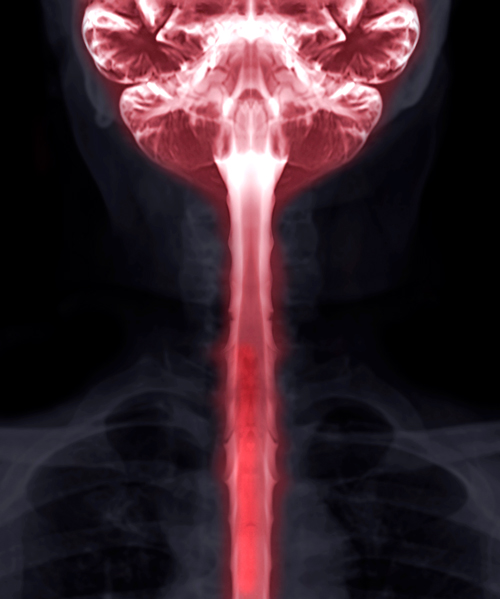

La mielografía —o mielograma— es un estudio de imagenología realizado por un radiólogo. Utiliza contraste y rayos X o una tomografía computarizada para encontrar alguna anomalía en el canal vertebral que tenga que ver con la médula espinal, las raíces nerviosas u otros tejidos.

El contraste se inyecta en la columna vertebral antes del procedimiento para que se diluya con el líquido cefalorraquídeo. Este aparece en los rayos x, lo que permite al radiólogo apreciar con mayor claridad la médula espinal, el espacio subaracnoideo y otras estructuras cercanas que con una radiografía ordinaria.

Una mielografía puede mostrar la médula espinal, los nervios espinales, las raíces nerviosas y los huesos en la columna. También revelará si algo está presionando la médula o los nervios. Las condiciones que se pueden diagnosticar con este estudio incluyen: